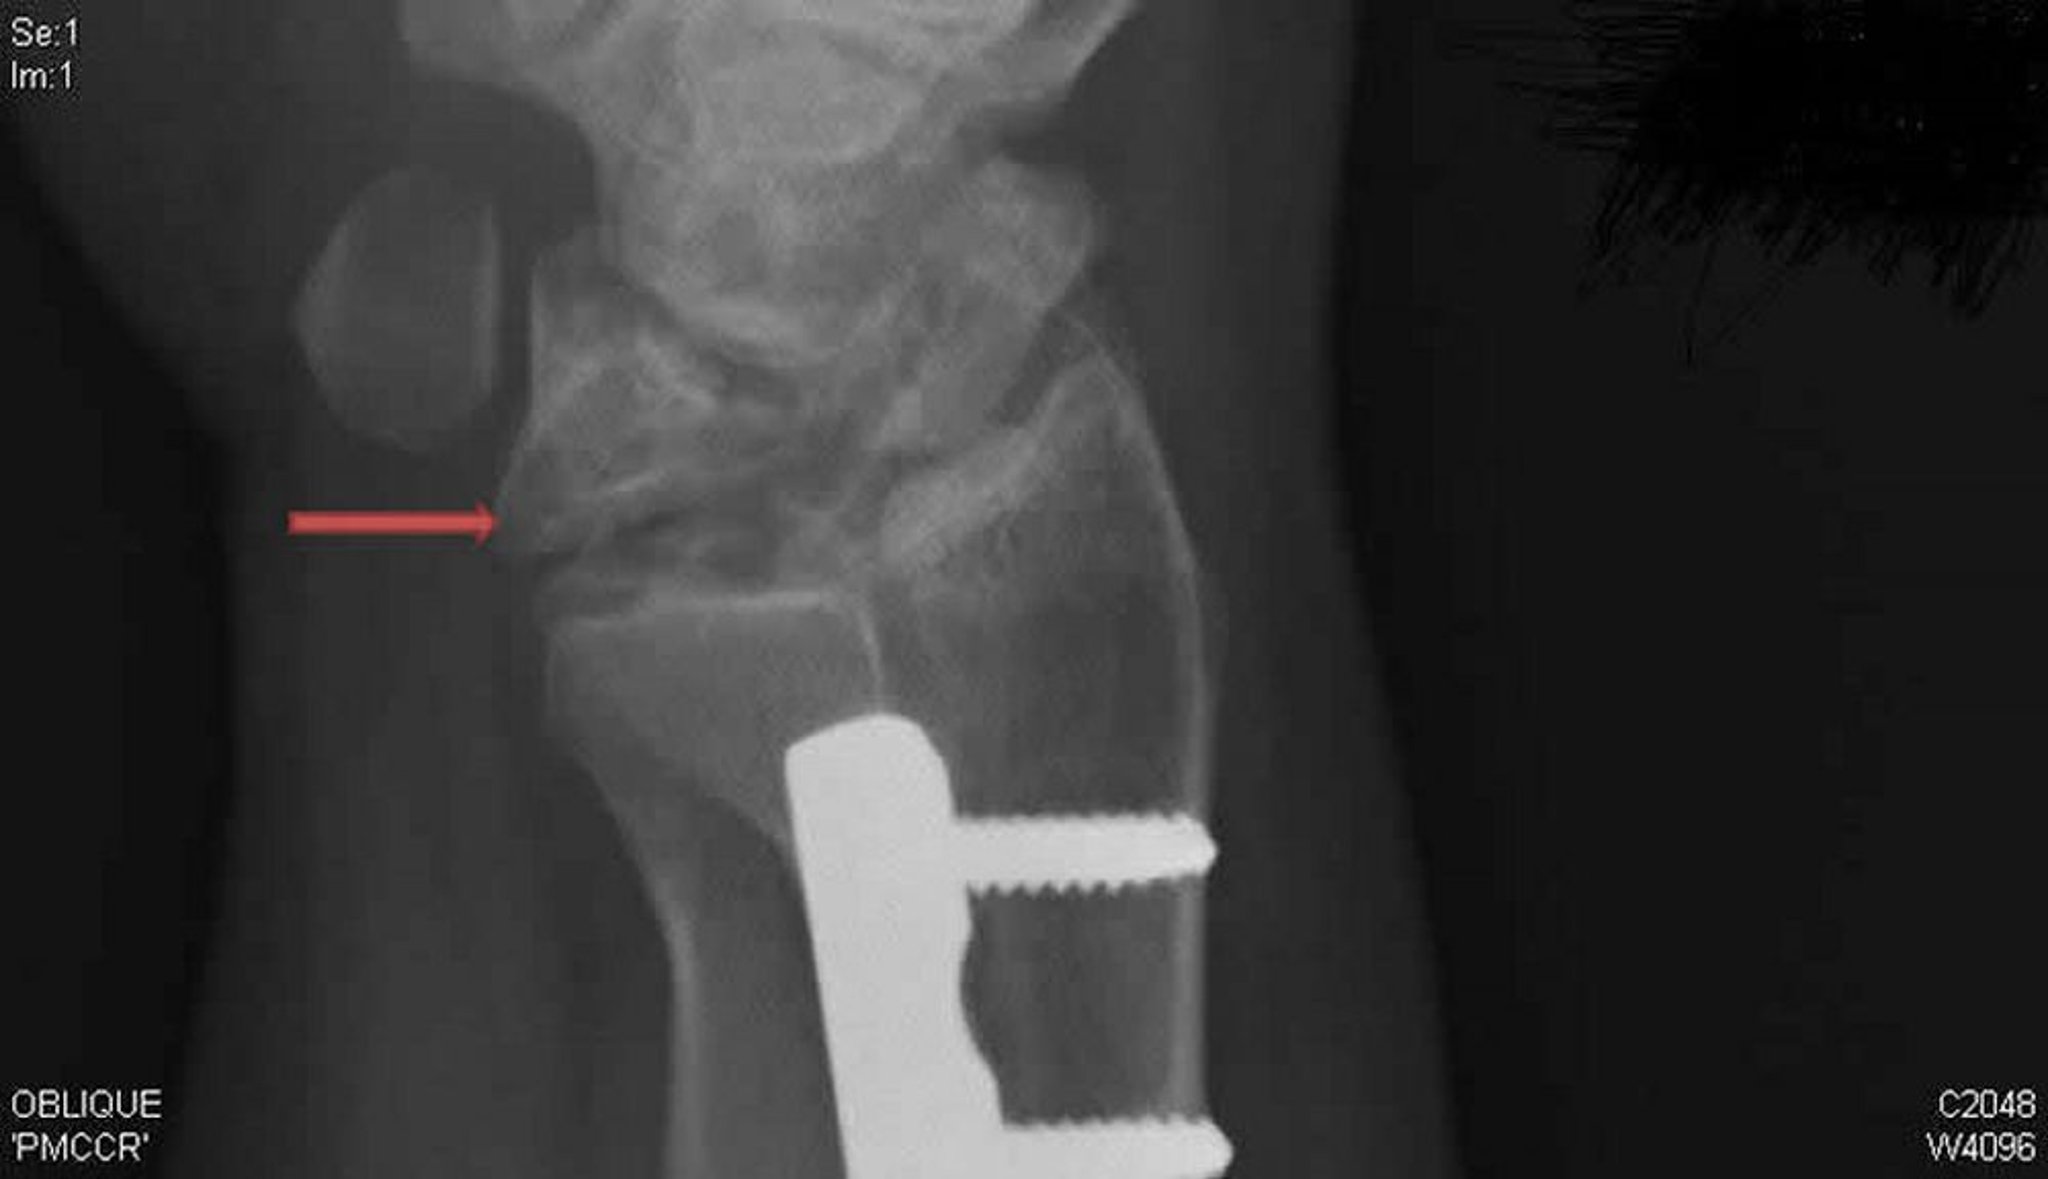

Morbus Kienböck (schräge Röntgenaufnahme)

Diese schräge Röntgenaufnahme des rechten Handgelenks zeigt die Kienböck-Krankheit. Beachten Sie den Kollaps und die Fragmentierung des Os lunatum (Pfeil), die in der posteroanterioren Ansicht nicht erkennbar war.

X-ray courtesy of David R. Steinberg, MD.